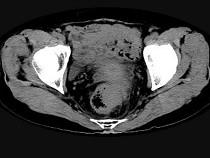

问题 男,56岁,排便形状改变,便不尽感,CT检查如图所示,下列说法正确的是()

选项 A.肠壁上有蒂状新生物 B.其表面光滑,边界清楚 C.肠腔未见狭窄 D.此为直肠息肉 E.此为直肠癌

答案 E